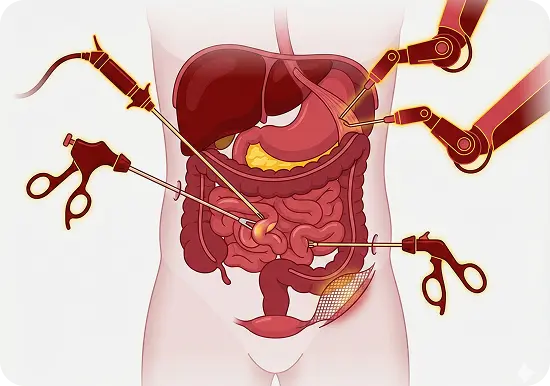

Pancreatic Surgery

- Whipple procedure (Pancreaticoduodenectomy)

- Distal and total pancreatectomy

- Minimally invasive and robotic-assisted pancreatic surgery

- Surgical management of pancreatic cysts and neuroendocrine tumour

- Vascular resections in pancreatic cancer surgery

- Surgical drainage of pancreatic pseudocysts

- Necrosectomy for infected pancreatic necrosis

- Surgery for chronic pancreatitis

Biliary & Liver Surgery

- Hepatectomy for liver tumours and metastases

- Bile duct resections and reconstructions

- Surgery for bile duct injuries, strictures, and gallbladder stones

- Management of gallbladder cancer

- Liver cyst and abscess drainage procedures

Gastrointestinal Oncology

- Surgery for stomach and colorectal cancers

- HIPEC (Hyperthermic Intraperitoneal Chemotherapy) for advanced GI cancers

- Minimally invasive and robotic-assisted pancreatic surgery

- Laparoscopic and robotic-assisted gastrointestinal surgeries

Benign GI Conditions

- Surgery for gastrointestinal stromal tumours (GISTs)

- Fundoplication for GERD and hiatal hernias

- Surgery for small bowel obstructions and diverticular disease

- Management of achalasia and esophageal motility disorders

Advanced Minimal Access Surgery

- Laparoscopic and robotic gastrointestinal surgeries

- Keyhole surgery for hernia repairs (inguinal, incisional, and diaphragmatic hernias)